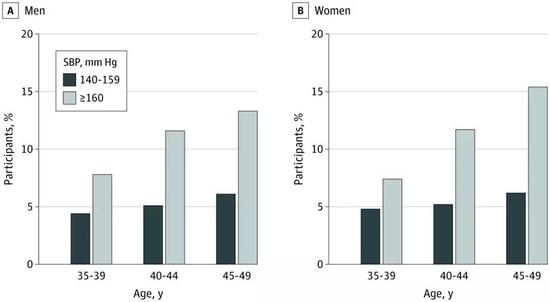

参与者的年龄分布和血压状况有超过15%的ISH患者收缩压已经在160mmHg以上,但在全部的ISH患者中,只有13.3%接受了相应治疗。没有接受过治疗的患者中,则只有6.8%意识到自己患有高血压。

就算收缩压高到160mmHg以上,男性和女性ISH患者的知晓率,分别也只有13.3%和15.4%。与China PEACE课题中高血压患者整体44.7%的知晓率相比,本次研究中这不到15.4%的相对最高值,根本就不及格。

不同年龄、不同血压值患者的知晓率对比

不同年龄、不同血压值患者的知晓率对比用研究团队在论文中的话说,就是“中青年人对基于医院的心血管预防项目参与度低,更难以意识到及早控制心血管危险因素的长期获益,从而更不愿意就医治疗和改变生活方式。”